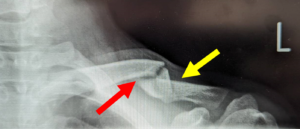

鎖骨は皮膚の直下にあり、表面に筋肉による被覆がほぼないため、骨折部が隆起し肉眼的に確認できることがしばしばあります。この肉眼的な膨隆がまるでテントが張られているようにみえるのでtentingといいます。

転位に伴う骨折部の肉眼変化(Tenting 赤矢印)

写真:遷延癒合(=骨折線が明確となり、骨折縁がなだらかになる:赤矢印)

第三骨片は癒合完了(黄矢印)、患者より提供